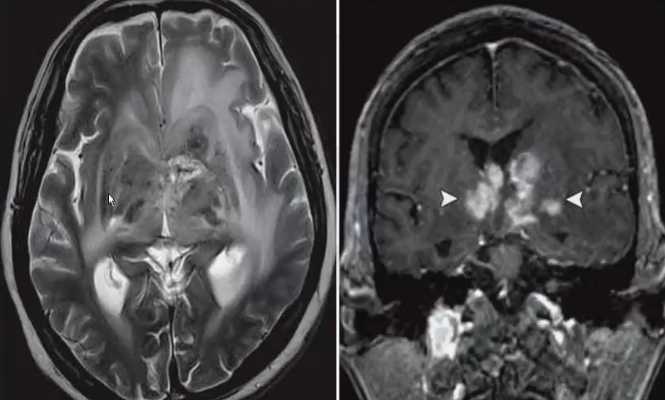

❖ 常为多发病灶,也可单发。典型影像学表现为肿块累及深部灰质结构,脑室旁区和胼胝体。

❖ MRI表现:平扫大多呈等或略长T1、等或长T2信号,边界较清楚,增强呈均匀明显强化,坏死囊变少见。常包埋脑室生长,侵犯半球深部脑室周围白质、胼胝体、基底节,室管膜下。